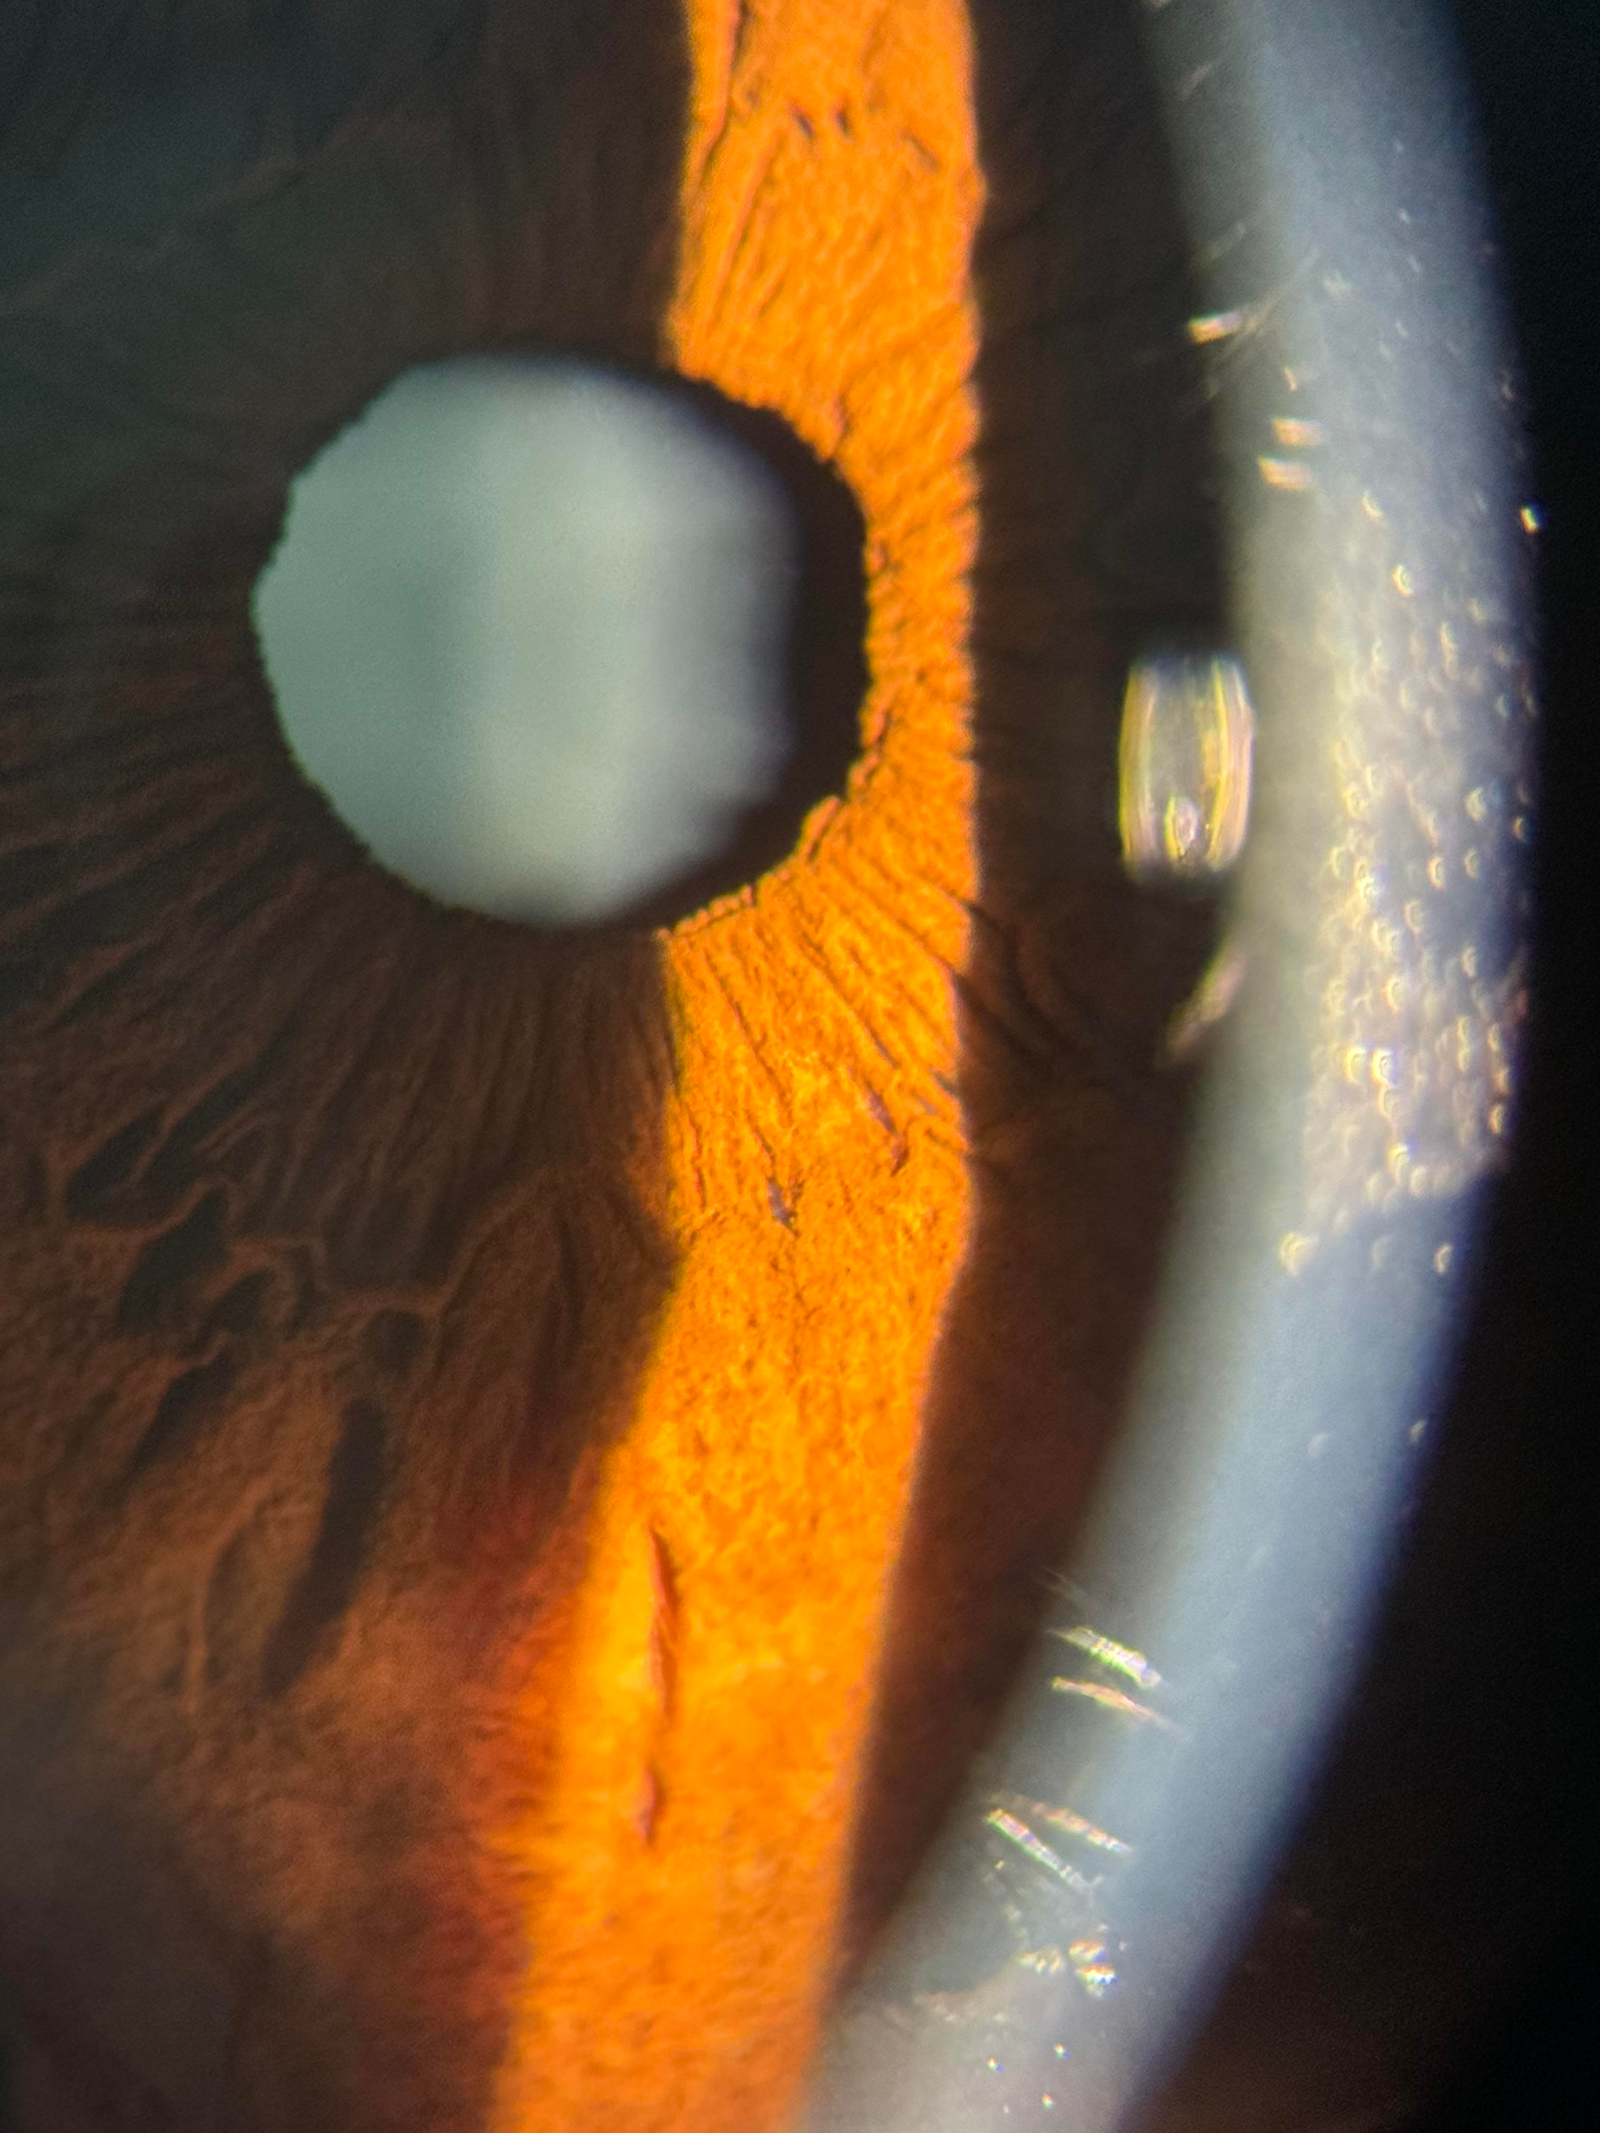

Look for a clinic that invests in modern diagnostic equipment – such as optical coherence tomography, digital retinal imaging and corneal topography – and stays current with advances in eye care. Continuous professional development ensures that your optometrist understands the latest research and treatment modalities and can offer evidence‑based care. Modern technology leads to more accurate assessments and access to a wider range of treatment options.